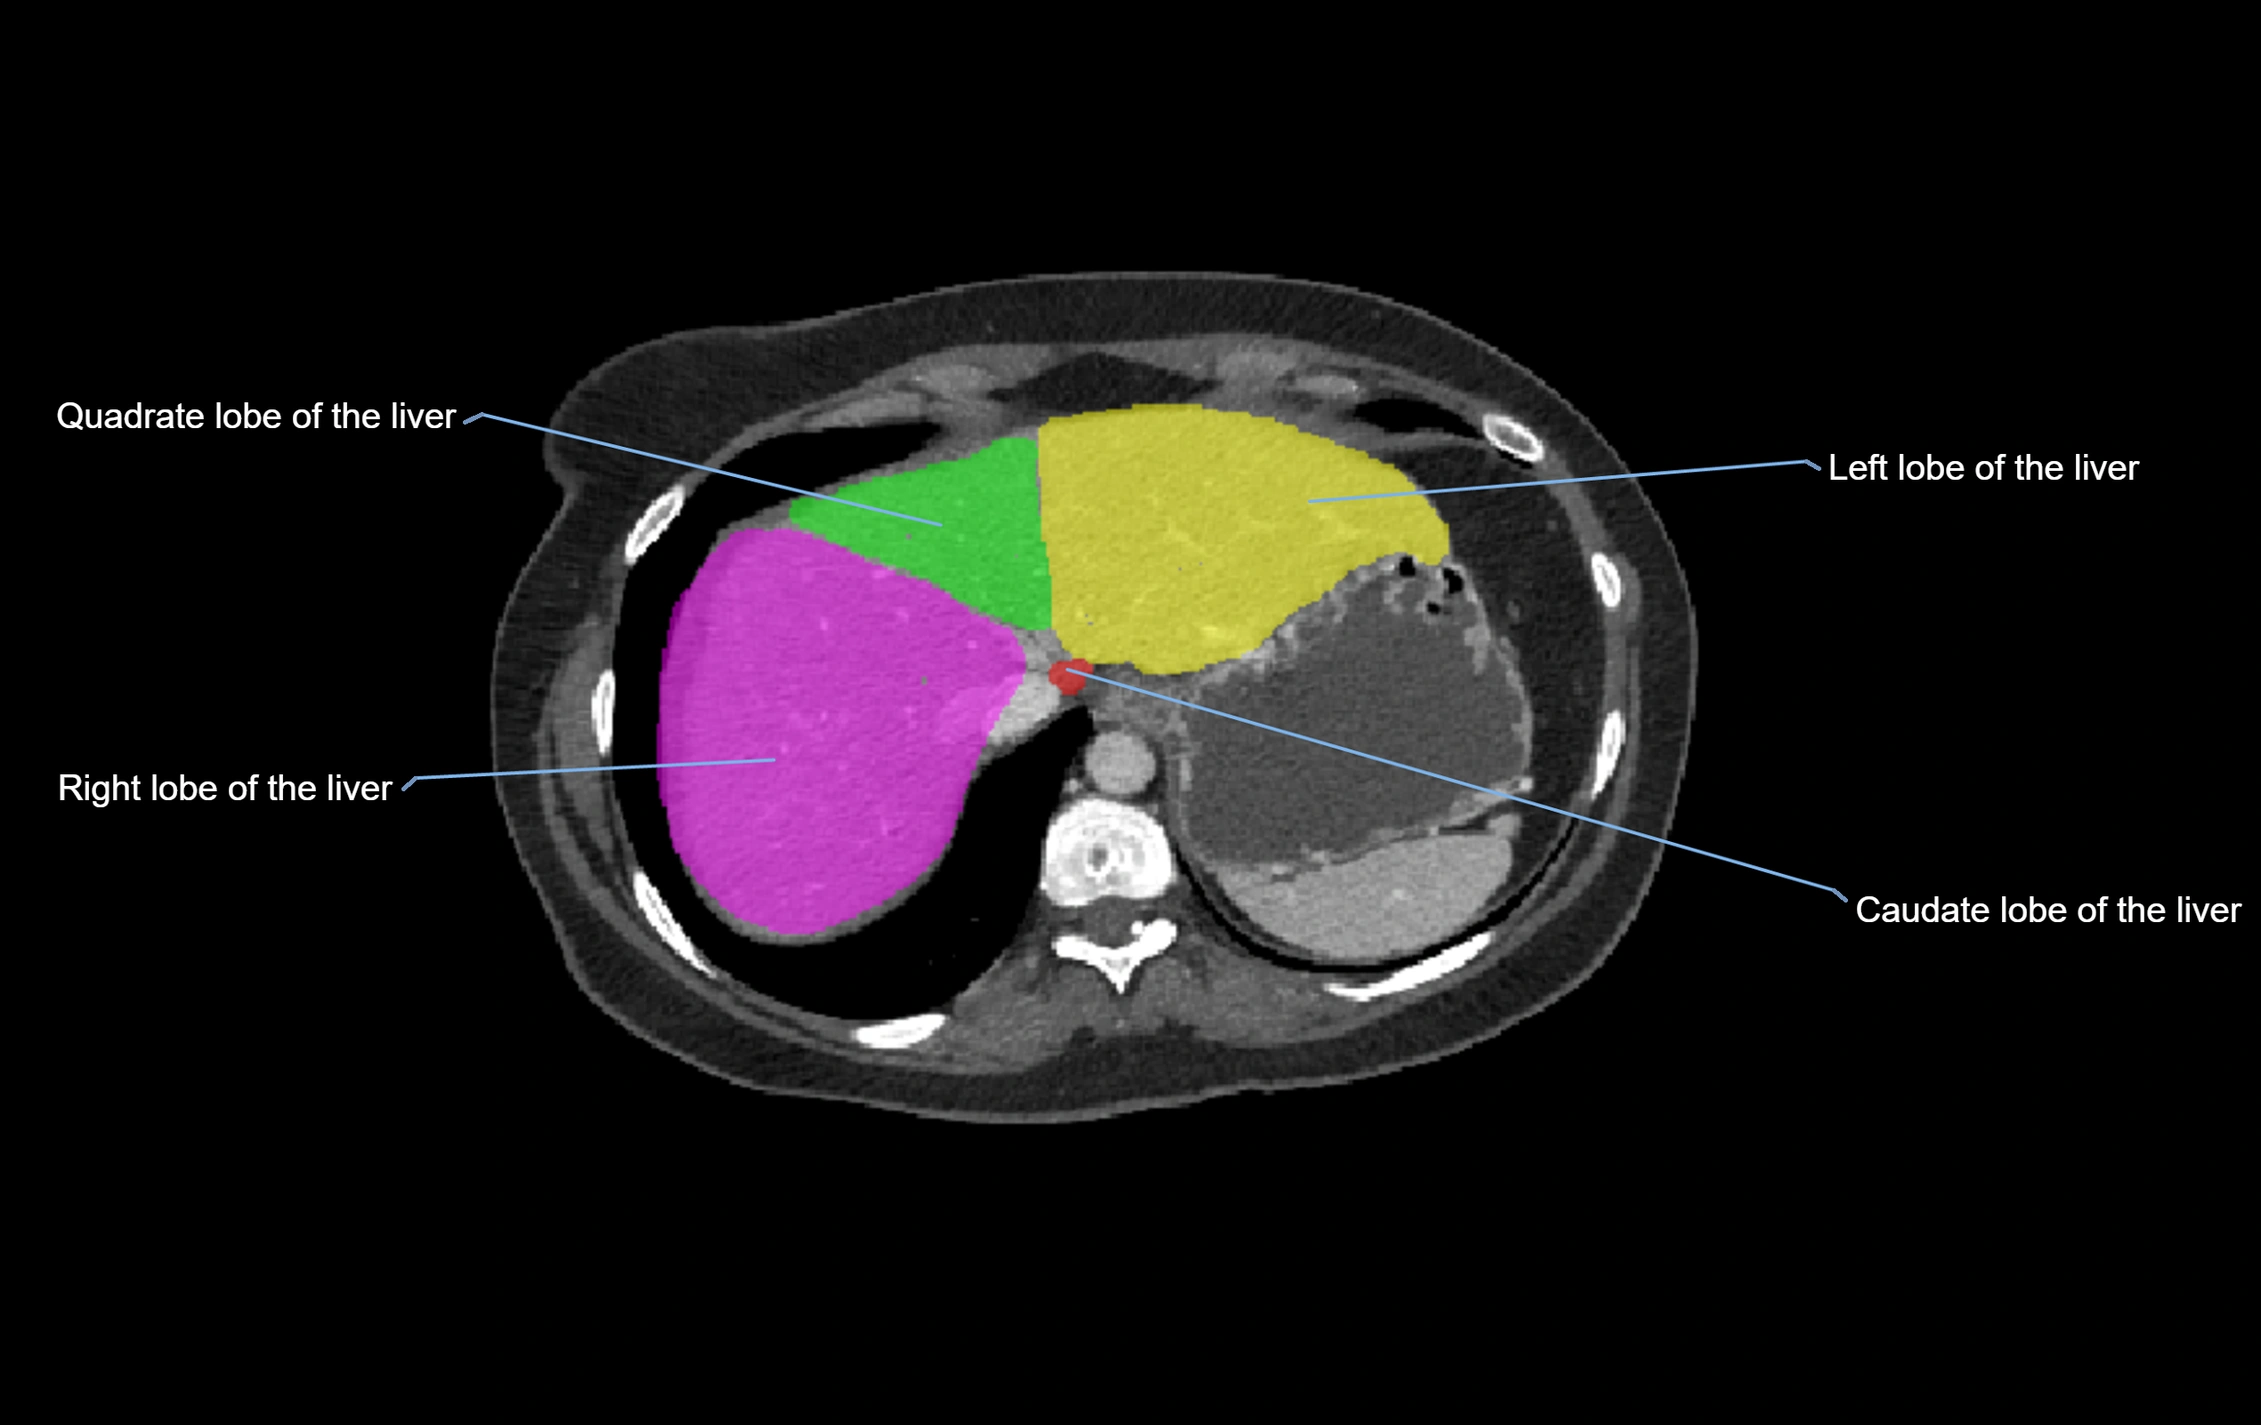

CT Image

image